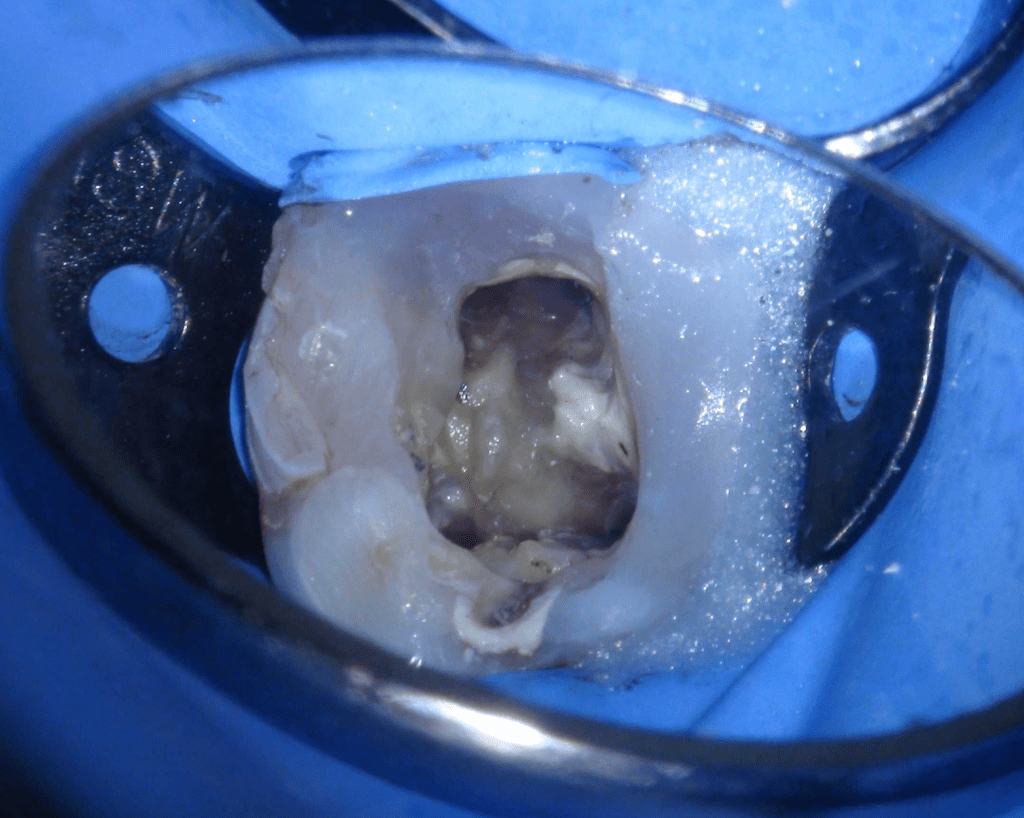

Reco preendo + 4 conductos molar superior